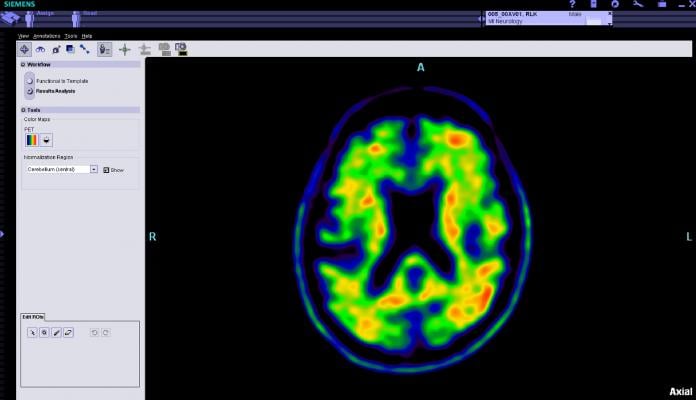

The IDEAS study will assess the impact of a brain PET scan to detect amyloid plaques on patient-oriented outcomes. These plaques are a core feature of Alzheimer’s disease in patients with mild cognitive impairment (MCI) or dementia of uncertain cause. Medicare will cover amyloid PET when the scan is conducted in accordance with the IDEAS-Study requirements.